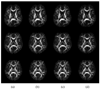

This article presents two related advancements to the diffusional kurtosis imaging estimation framework to increase its robustness to noise, motion, and imaging artifacts. The first advancement substantially improves the estimation of diffusion and kurtosis tensors parameterizing the diffusional kurtosis imaging model. Rather than utilizing conventional unconstrained least squares methods, the tensor estimation problem is formulated as linearly constrained linear least squares, where the constraints ensure physically and/or biologically plausible tensor estimates. The exact solution to the constrained problem is found via convex quadratic programming methods or, alternatively, an approximate solution is determined through a fast heuristic algorithm. The computationally more demanding quadratic programming-based method is more flexible, allowing for an arbitrary number of diffusion weightings and different gradient sets for each diffusion weighting. The heuristic algorithm is suitable for real-time settings such as on clinical scanners, where run time is crucial. The advantage offered by the proposed constrained algorithms is demonstrated using in vivo human brain images. The proposed constrained methods allow for shorter scan times and/or higher spatial resolution for a given fidelity of the diffusional kurtosis imaging parametric maps. The second advancement increases the efficiency and accuracy of the estimation of mean and radial kurtoses by applying exact closed-form formulae.